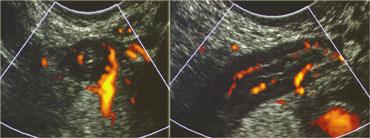

TRÁI: Ruột thừa bình thường có kích thước nhỏ, có thể đè xẹp, không có tín hiệu Doppler và không được bao quanh bởi lớp mỡ viêm. PHẢI: Ruột thừa viêm có kích thước lớn, không thể đè xẹp và tăng sinh mạch máu, được bao quanh bởi mô tăng âm, không thể đè xẹp, đại diện cho mạc treo ruột thừa nhiều mỡ

Hình ảnh điển hình của ruột thừa viêm là một cấu trúc hình ống dài như xúc xích, có các lớp đồng tâm, không thể đè xẹp, được xác định ở vị trí cố định tại điểm đau tối đa (Hình).

Đường kính tối đa trung bình là 9mm với biên độ dao động từ 7 đến 17mm. Trong 30% trường hợp, sỏi phân (fecolith) trong lòng ruột thừa được tìm thấy gây tắc nghẽn thực sự.

Từ 6 đến 12 giờ sau khi khởi phát triệu chứng, tình trạng viêm lan rộng đến lớp mỡ lân cận của mạc treo ruột thừa, lớp mỡ này trở nên lớn hơn, tăng âm hơn và kém đè xẹp hơn.

Về sau, mô mỡ này có xu hướng tăng thể tích xung quanh ruột thừa: đây là mạc treo và mạc nối lớn đã di chuyển về phía ruột thừa nhằm cố gắng bao bọc ngăn chặn tình trạng thủng sắp xảy ra.

Mức độ tưới máu thành ruột thừa có thể tăng rõ rệt hoặc vắng mặt do áp lực trong lòng ruột cao kèm theo hoại tử thiếu máu cục bộ; tuy nhiên, luôn có sự tăng sinh mạch máu trong mô mỡ xung quanh trực tiếp.